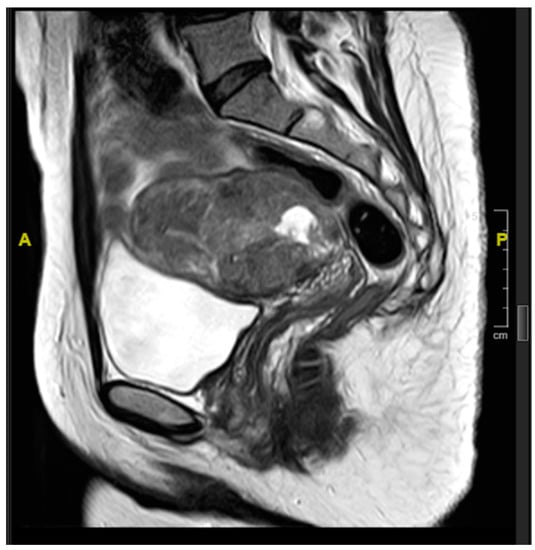

2. Case Presentation